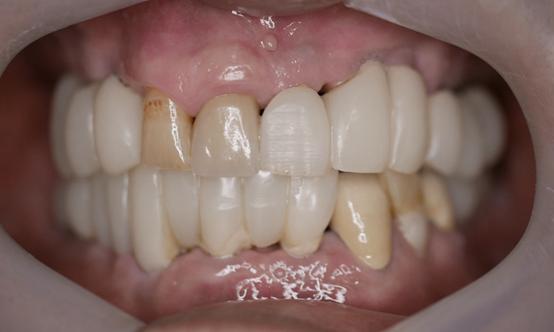

55

歲的陳先生長年來為牙齒問題所苦,前陣子受不了終於來診所做治療,原來是因為上排全口無牙,一直以來都是帶活動假牙,55

歲的他看起來外型還算年輕,但是活動假牙讓他很沒自信,吃東西也大受影響。